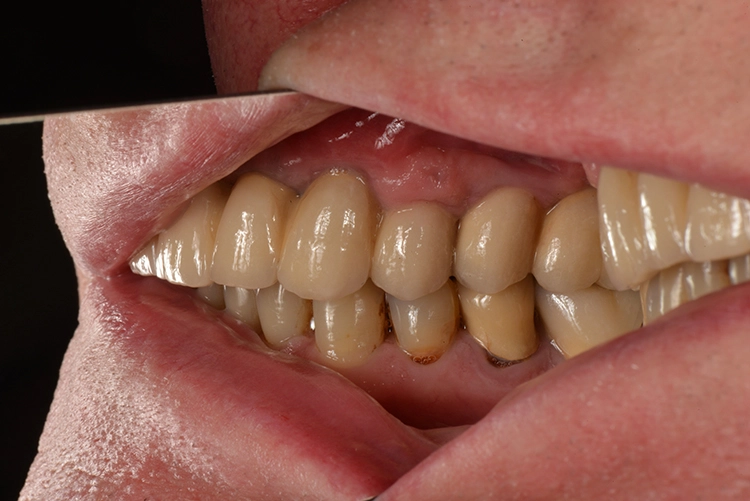

Der 64-jährige Patient ist leidenschaftlicher Camper und störte sich an seiner „schaukelnden“, nur noch auf drei Pfeilern abgestützten Teleskopprothese im Oberkiefer. Sie sei ihm im Beisein seiner Camper-Kollegen bereits des Öfteren beinahe „rausgefallen“.

Zudem sei seine Kau- und Sprechfunktion deutlich einschränkt. Er wünschte sich „etwas langfristig Festes“. Für den Patienten bestand keine Alternative zu einer implantatgetragenen Versorgung, eine herausnehmbare Versorgung in Form einer Totalprothese kam für ihn nicht in Frage.

Der Patient ist Nichtraucher mit gutem Allgemeinzustand und nach Anamnese ohne kritische oder für einen eventuell notwendigen Knochenaufbau risikobehaftete Komorbiditäten [3]. Seine Teleskopprothese im Oberkiefer war nur noch über die drei Pfeilerzähne 13, 22 und 23 verankert.

Die Implantatmaße und -positionen sowie der Umfang der Sinusbodenelevation wurden dabei in Sinne eines „backward planning“ anhand von DVT-Aufnahmen bestimmt. Zahn 13 sollte noch vorübergehend erhalten bleiben, um zusammen mit den bleibenden Zähnen 23 und dem entsprechend kariesbehandelten Zahn 24 bis zur Fertigstellung der definitiven Restauration der alten Teleskopprothese als Interimsersatz Halt zu geben. Als definitive Versorgung wurden drei VMK-Brücken auf NEM-Gerüsten vorgesehen. Damit sollte auch die natürliche Bezahnung im Unterkiefer von 37 bis 47 abgestützt werden.